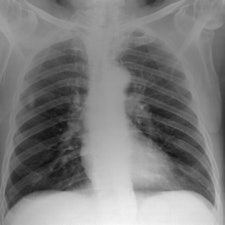

They tested the model in a "virtual clinical trial" in which four experienced image evaluators graded images of average and obese adult patients at different potentials, receptor doses, and scatter rejection techniques on an Agfa HealthCare CR system using MD-4.0 phosphor plates. The quality of the images was evaluated using visually graded analysis. The researchers also assessed the influence of rib contrast.

For average-sized patients, image quality improved when tube potential was reduced compared with the reference (102 kVp) and no scatter rejection was indicated. For obese patients, it has been shown that an antiscatter grid is indicated and should be used in conjunction with as low a tube potential as possible (while allowing exposure times, 20 msec), the researchers wrote. It is also possible to reduce receptor air kerma by 50% without adversely influencing image quality. They also found rib contrast did not interfere at any tube potential.

In 50 average patients who were reconstructed without scatter rejection, readers gave higher marks for images acquired with lower tube potential (kVp) settings, demonstrating that image quality improves with lower kVp, the researchers said. Visual grading analysis system scores ranged from 0.41 for 50 kVp to 0.03 for 109 kVp, but there was very little difference between image quality at tube potentials greater than 102 kVp (0.03 at 109 kVp to 0.07 at 150 kVp), according to the authors.